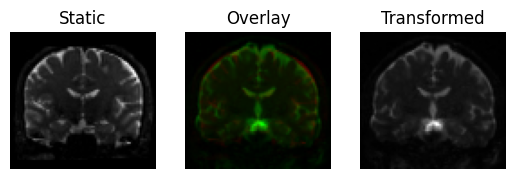

Alternatively, you can also use the register_dwi_to_template function that needs to also know about the gradient table of the DWI data, provided as a tuple of (bvals_file, bvecs_file). In this case, we are going to move the diffusion data to the B0 image (the opposite of the previous examples), which reverses what is the “moving” image and what is “static”.

<Figure size 640x480 with 3 Axes>

Same again, using the dwi_to_template functional interface.